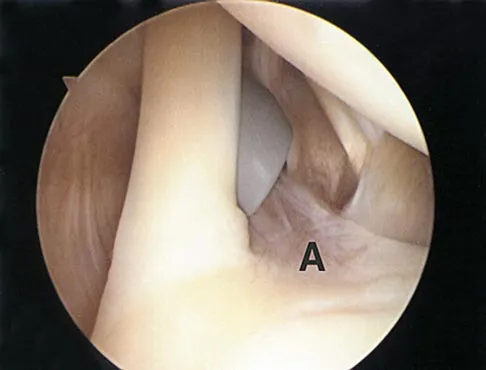

In the arthroscopic photograph shown in Figure 5, the structure labeled "A" functions primarily as a restraint to translation of the humeral head in what direction?

Explanation